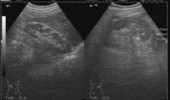

- Самым достоверным методом диагностики липом в области лица является ультразвуковое исследование опухоли. Метод безболезненный. Липома при нем обнаруживается наличием гипоэхогенного образования в жировой ткани, округлой формы, имеющего капсулу.